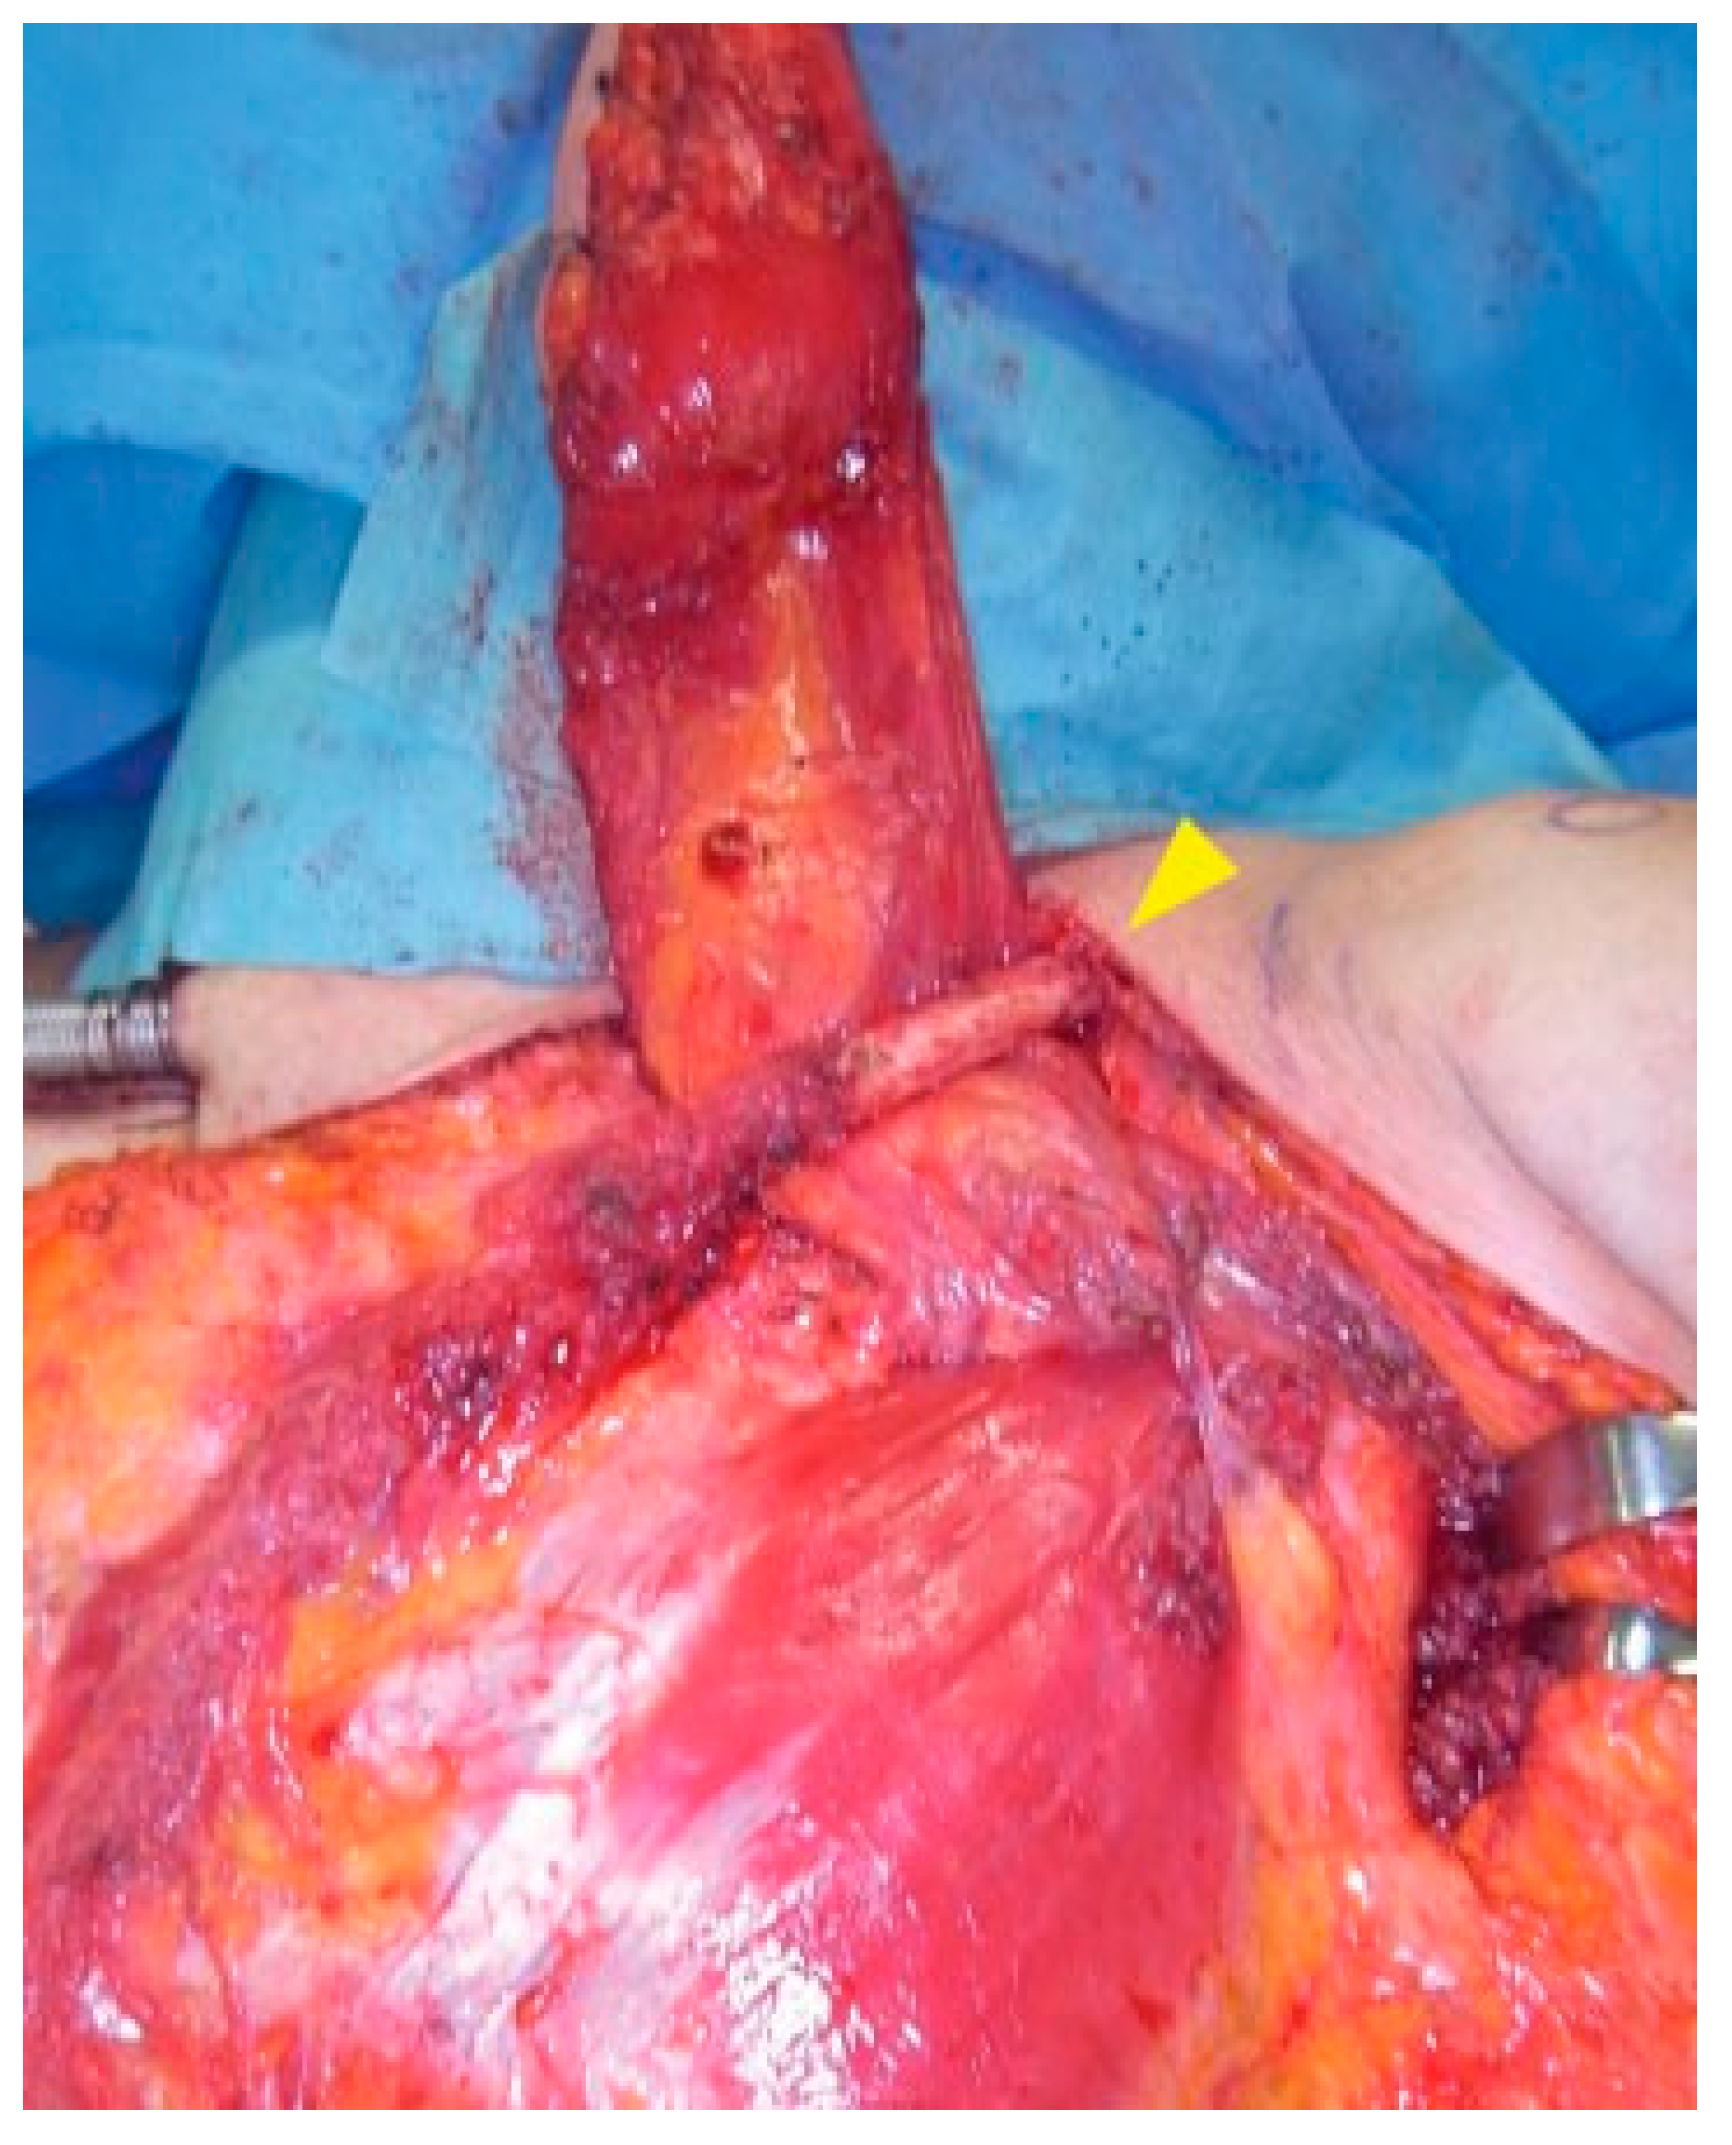

An 81-year-old Japanese woman with squamous cell carcinoma on the left side of the tongue was referred to our department. The tumor extended over a midline contralaterally and a swollen lymph node in Level IIA with fixation around soft tissue, which contrast-enhanced computed tomography (CT) showed, was palpable. The lesion was staged as cT3N1M0 according to the TNM Classification of Malignant Tumors (7th Edition, UICC) [6]. But there were two lymph nodes with an irregular contrast effect in Levels IIA and B in contrast-enhanced magnetic resonance imaging besides the obvious metastatic lymph node by contrast-enhanced CT that were suspected lymph node metastases (Figure 1). Therefore, RND, subtotal glossectomy, and simultaneous reconstruction using a PMMCF were performed. The PMMCF was elevated from the chest wall and moved upward. The clavicular periosteum around the pectoral branches of the thoracoacromial vessels was excised from the cervical and thoracic sides, and the periosteum on the inferior surface of the clavicle was detached and reflected to drop it downward [7,8]. The PMMCF was brought to the oral cavity via the subclavian route for reconstruction of the defect of the tongue (Figure 2).

Figure 2. Bringing pectoralis major myocutaneous flap to the oral cavity via the subclavian root (arrowhead: left clavicle).